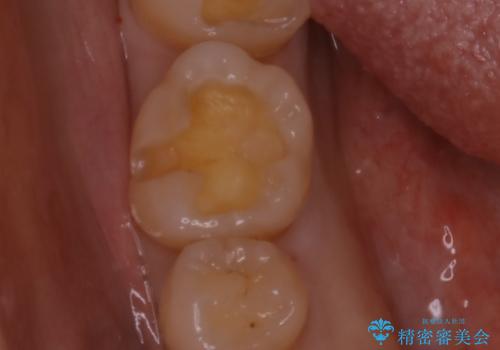

- 矯正治療が終了して歯並びが綺麗になると、元々入っていた銀歯が気になってきたとのことで適合の良いセラミックへのやり替えを行いました。

適合不良の補綴物は二次的な虫歯発生のリスクが高まります。

自費診療で用いられる材料は保険適応の材料に比べて、より精密で適合の良い被せ物作ることができるため、長期的な虫歯のリスクを大幅に減らすことが可能です。